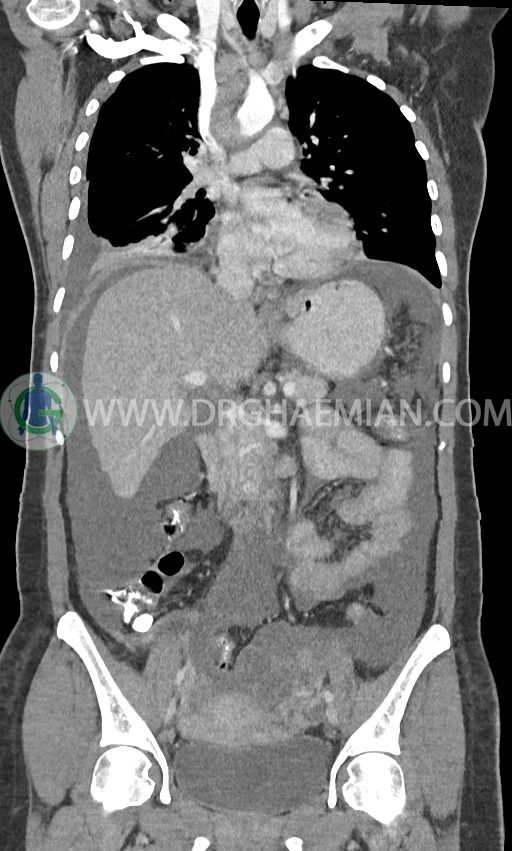

در سی تی اسکن اسپیرال ریه، مدیاستن و شکم و لگن با کنتراست خوراکی و وریدی (مولتی دیدکتور 16 با مقاطع ظریف و بازسازی های ساژیتال و کرونال) :

لنفادنوپاتی فراون با حداکثر SAD=25mm در مدیاستن

لنفادنوپاتی با حداکثر SAD = 12mm در سوپراکلاویکل چپ (level 4) و در level 6 و level 7

pleural effusion قابل توجه دوطرفه همراه با passive collapse سگمان های بازال (با شدت بیشتر در سمت راست)

توده با حدود صاف و واضح به قطر 17mm درمدیال پستان راست و با حدود لوبوله به قطر 20mm در قسمت خارجی- فوقانی پستان راست

اسیت قابل توجه در حفره شکم و لگن

انفیلتراسیون تومورال در قسمت های مختلف اومنتوم (omental cake)، به ویژه در قسمت تحتانی حفره شکم و لگن